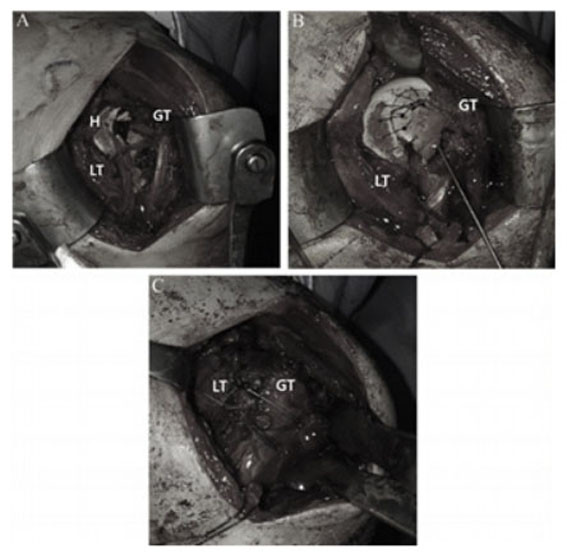

Á¤Çü¿Ü°ú ¼ö¼ú °ü·Ã ±¹Á¦ÇмúÁöÀÎ ¡®Journal of Arthroscopy and Joint Surgery¡¯¿¡ °ÔÀçµÈ ¡®Reverse Hill-Sachs lesion with a greater and lesser tuberosity fracture of the humerus due to posterior shoulder dislocation¡¯ ³í¹®Àº ¾î±ú Å»±¸ ¹× ±¤¹üÀ§ ȸÀü±Ù°³ º´º¯¿¡ ´ëÇÑ Ä¡·á¹ýÀ» ¿¬±¸ÇÑ ³í¹®ÀÌ´Ù.

À̹ø ¿¬±¸¿¡¼ À¯À缺±³¼ö´Â ¾î±ú Å»±¸¿Í µ¿¹ÝµÈ »ó¿Ï°ñ ±ÙÀ§ºÎ °ñÀý ȯÀÚ¿¡°Ô ºÀÇÕ ³ª»ç ¹× ³ª»ç¸ø °íÁ¤¼úÀ» ½ÃÇàÇÏ¿© Áõ»óÀÌ È£ÀüµÇ´Â °á°ú°¡ ³ªÅ¸³µÀ½À» È®ÀÎÇß´Ù.

À¯À缺 ±³¼ö´Â ¡°À̹ø ¿¬±¸¸¦ ÅëÇØ ±¤¹üÀ§ ȸÀü±Ù°³ ¼Õ»óÀ¸·Î °íÅë ¹Þ´Â È¯Àڵ鿡°Ô È¿°úÀûÀÎ Ä¡·á¸¦ Á¦°øÇÒ ¼ö ÀÖÀ» °ÍÀ¸·Î ±â´ëµÈ´Ù´Â Á¡¿¡¼ À¯ÀǹÌÇÑ ¿¬±¸¿´´Ù°í »ý°¢ÇÑ´Ù. ¾ÕÀ¸·Îµµ °ü·Ã ¿¬±¸¸¦ Áö¼ÓÇÏ¿© º¸´Ù ³ªÀº Ä¡·á¹æÇâÀ» ȯÀڵ鿡°Ô Á¦½ÃÇÒ ¼ö ÀÖµµ·Ï ³ë·ÂÇϰڴÙ.¡±°í ÀüÇß´Ù.

| | ¡è¡è ¡ãºÀÇÕ ³ª»ç ¹× ³ª»ç¸ø °íÁ¤¼ú <»çÁøÁ¦°ø=õ¾È¾Æ»êÃæ¹«º´¿ø> | ¨Ï ¿Â¾ç½Å¹® | |